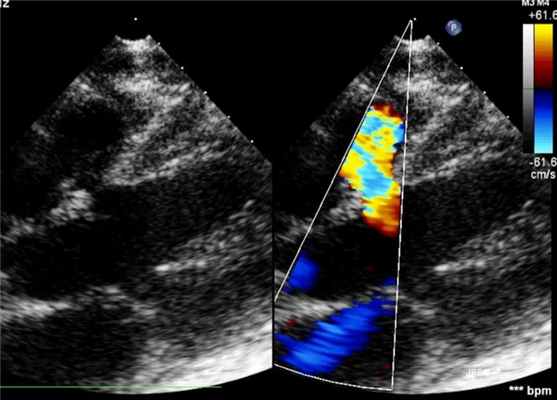

Для диагностики заболевания применяется рентгенография органов грудной клетки - она показывает увеличение сердца и легочного сосудистого рисунка. Также может быть назначена электрокардиограмма, которая показывает гипертрофию желудочков. Но нужно отметить, что при небольших дефектах эти исследования не всегда показательны, показатели могут быть в норме. Ключевой метод исследования при ДМЖП - эхокардиография. Она дает исчерпывающие анатомические и гемодинамические данные и позволяет установить диагноз.

Диагноз ставят на основании результатов эхокардиографии. Определяют в В-режиме, цветном доплеровском картировании наличие, количество, размер и расположение дефектов, с помощью спектрального доплера можно определить скорость потока сквозь дефект, направление сброса и давление внутри камер сердца.

Р ис. 1 ДМЖП в В-режиме.

Рис.2 ДМЖП в В-режиме и режиме ЦДК.